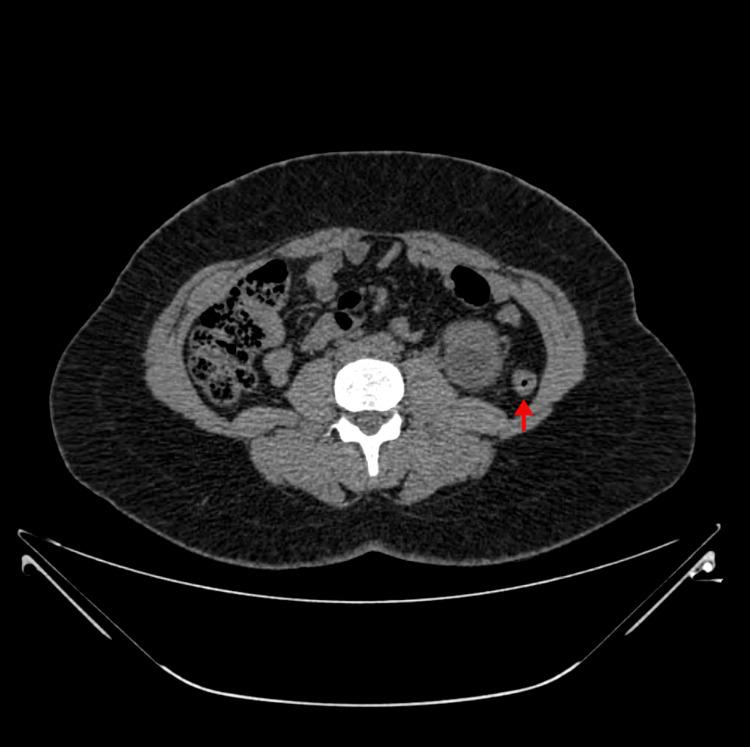

A retro-renal colon (RRC) is a rare but important anatomical variant to consider when planning percutaneous stone surgery. CT scanning of the abdomen is critical to detect this and to plan the surgical approach to avoid injury to the colon. In this case report, a 38-year-old woman with large obstructing bilateral symptomatic renal stones was found to have a left retro-renal colon on image review prior to left percutaneous nephrolithotomy. An open pyelolithotomy was performed to surgically remove the stone and to prevent any injury to the colon. An RRC can occur in up to 16% of patients undergoing percutaneous renal access. A CT scan is important to rule out this anatomical variant and to allow for surgical planning to avoid injury to the colon. The modern era of endourology has brought a significant reduction in open stone surgery. An open pyelolithotomy is still a safe option for stone removal if an RRC is detected preoperatively. Injury to the colon during percutaneous access can most commonly be managed conservatively. Occasionally open intervention may be required. An RRC detected on a preoperative CT scan may influence surgical planning and an open pyelolithotomy can be performed to safely remove renal stones and prevent colonic injury, especially in resource-limited settings.

肾后结肠(RRC)是一种罕见但重要的解剖变异,在规划经皮结石手术时需要考虑。腹部CT扫描对于检测这种情况并规划手术入路以避免结肠损伤至关重要。在本病例报告中,一名38岁患有双侧有症状的大型梗阻性肾结石的女性,在左侧经皮肾镜取石术前影像检查时发现有左肾后结肠。进行了开放性肾盂切开取石术以手术取出结石并防止对结肠造成任何损伤。肾后结肠在高达16%的接受经皮肾穿刺的患者中可能出现。CT扫描对于排除这种解剖变异并进行手术规划以避免结肠损伤很重要。现代腔内泌尿外科时代已使开放性结石手术显著减少。如果术前检测到肾后结肠,开放性肾盂切开取石术仍是取出结石的安全选择。经皮穿刺过程中对结肠的损伤通常可以保守处理。偶尔可能需要开放干预。术前CT扫描检测到肾后结肠可能会影响手术规划,并且可以进行开放性肾盂切开取石术以安全地取出肾结石并防止结肠损伤,特别是在资源有限的情况下。